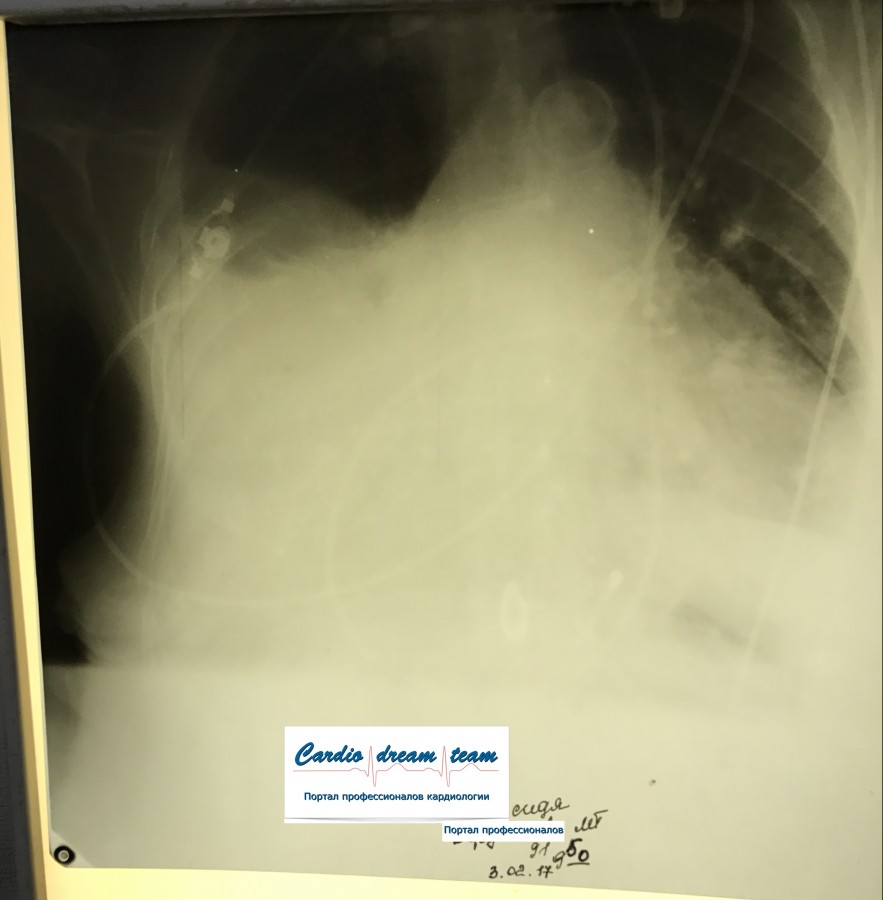

Тотальное затемнение слева - жидкость. Но жидкости не так и много. Всё-таки просматривается легочная ткань и при пункции получено всего 400 мл. Сидя в этом случае надо делать снимок. Или чтобы объем жидкости подсчитали спецы УЗИ.

IMG_4652--.jpg

IMG_4652--.jpg [ 484.49 KiB | Просмотров: 103586 ]